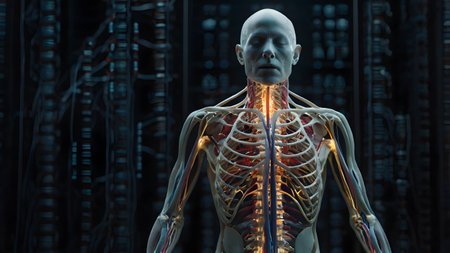

a human model with bones and muscles in a laboratory

This image showcases a detailed representation of the human nervous system using neon effects, emphasizing nerve pathways and anatomical structures against a dark backdrop.

Depicting the complexity of human anatomy --ar 3:2 Job ID: b50ee814-d31d-4470-8ac3-af000e98b3c5

a human model with bones and muscles in a laboratory